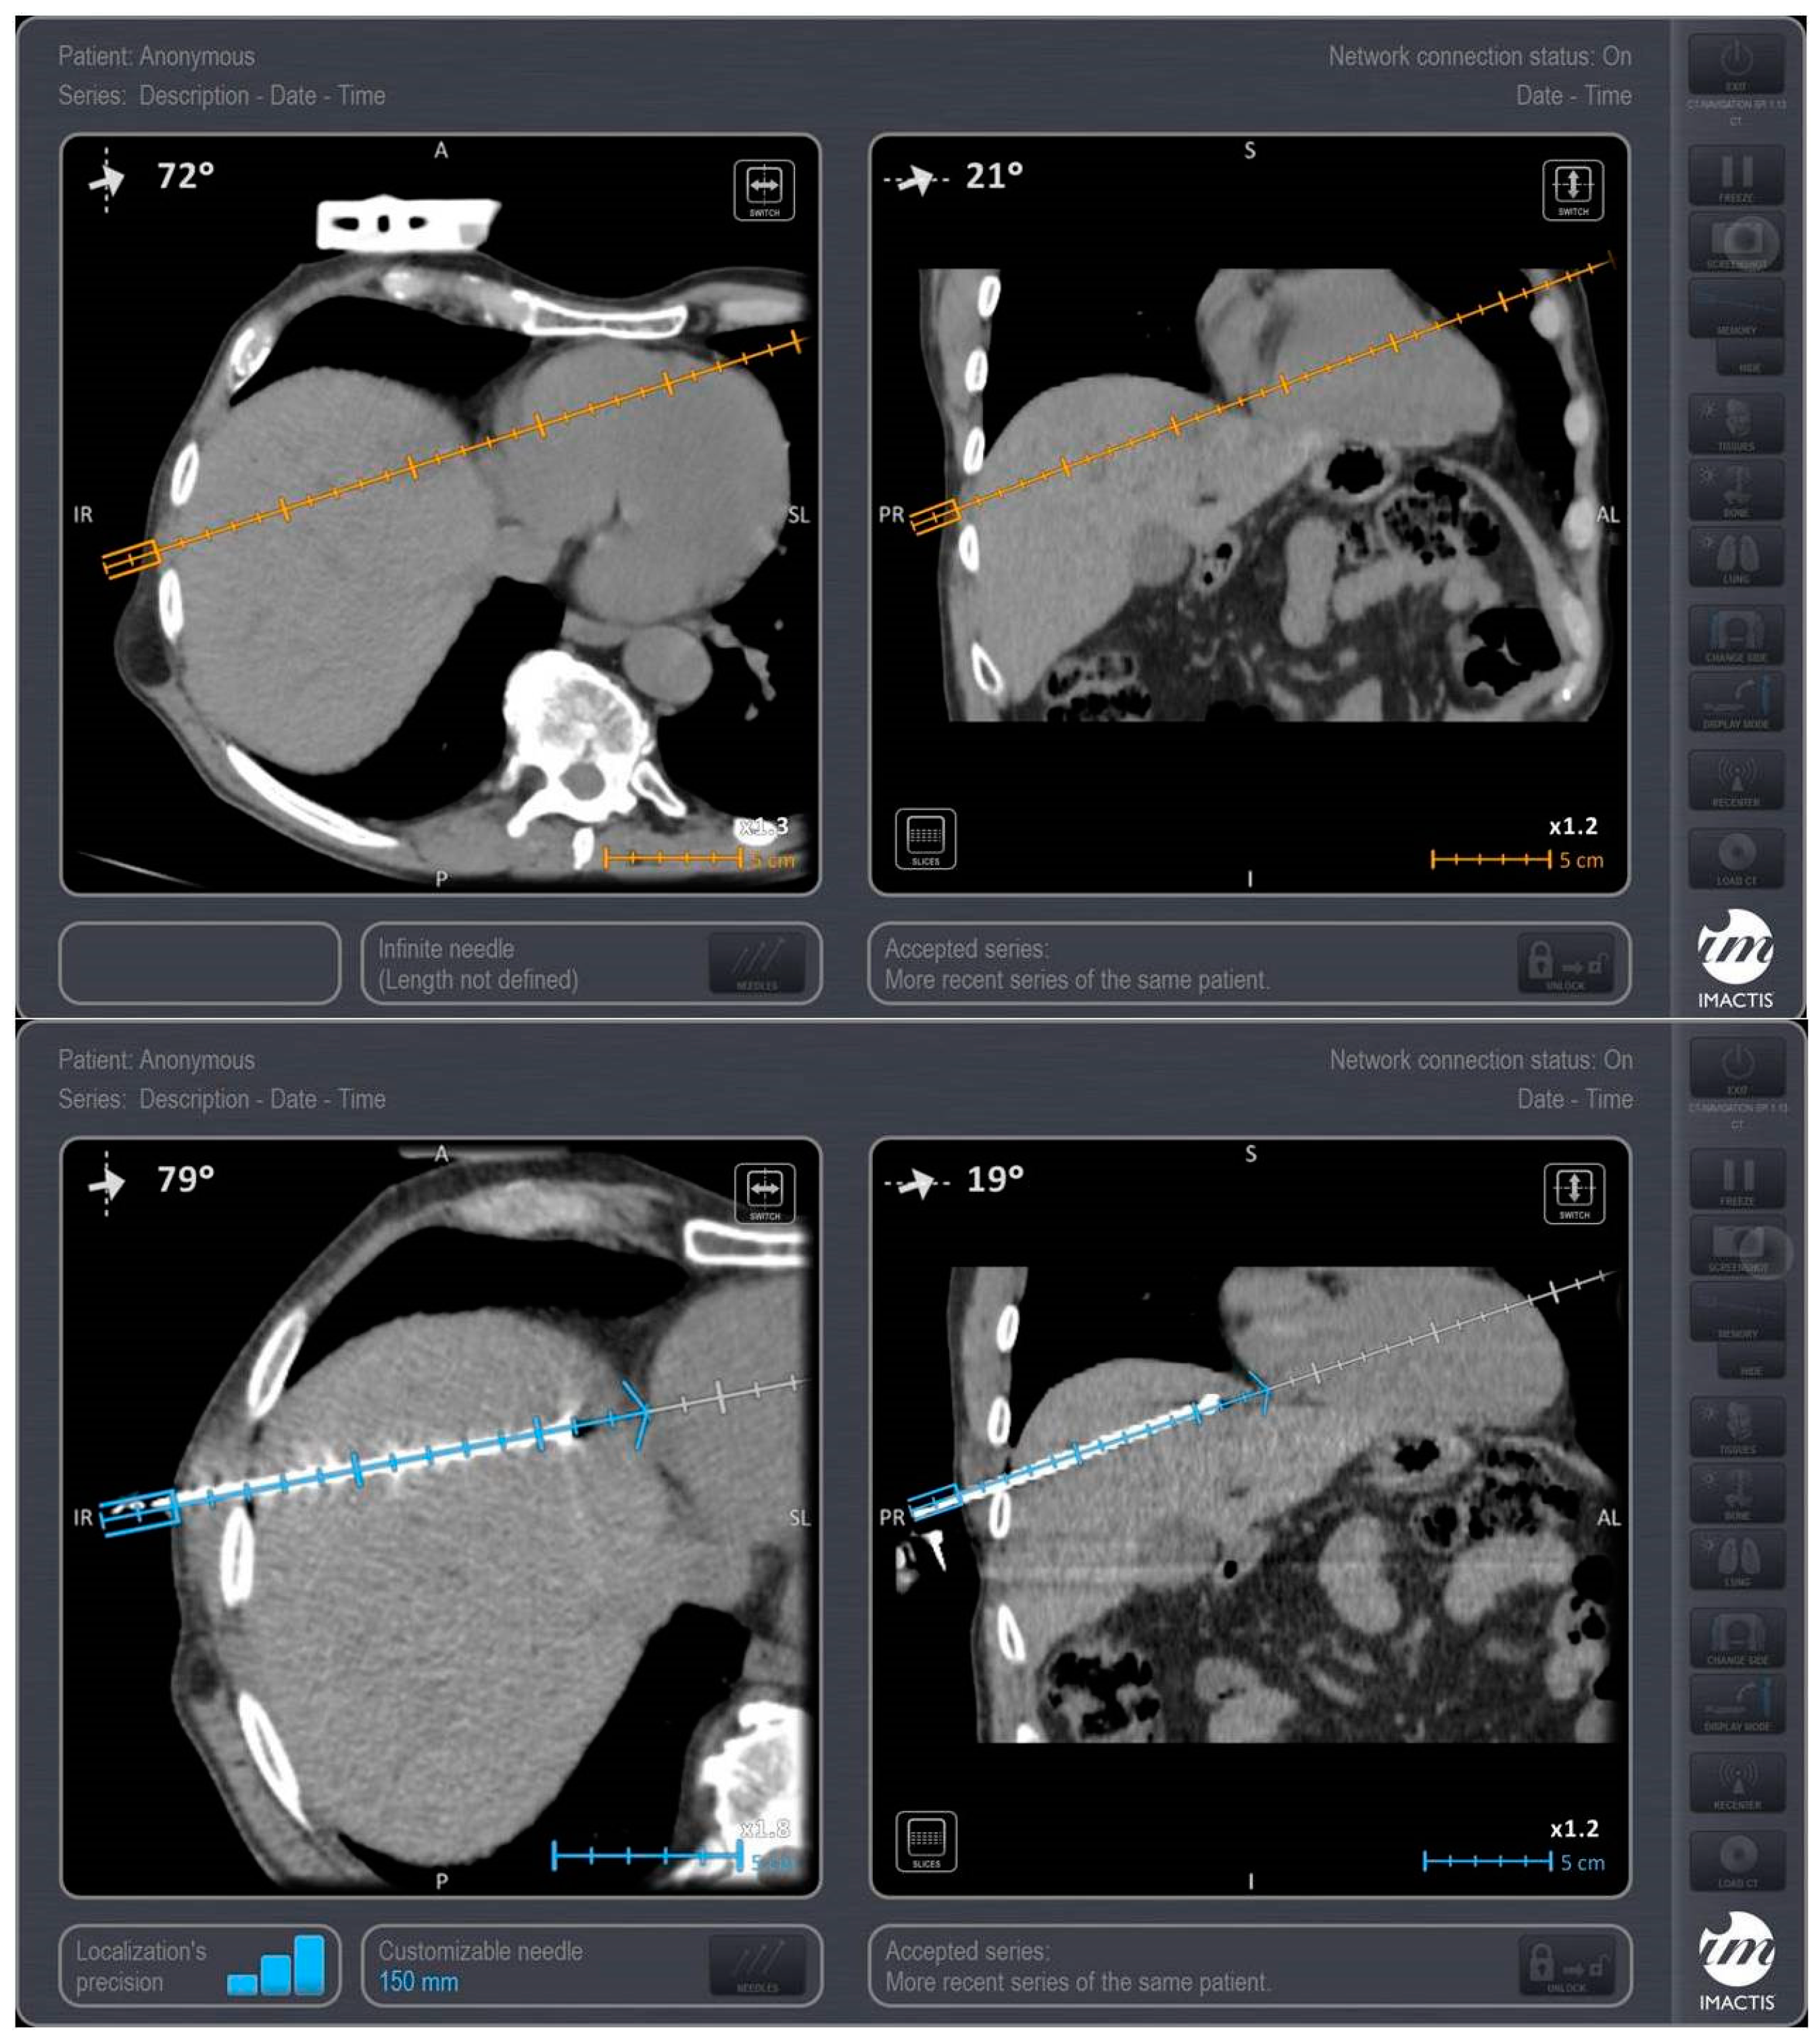

Trajectory planning and insertion of the microwave antenna were conducted using a commercially available navigation system for interventional radiology (IMACTIS SAS, Saint Martin d’Hères, France), (Figure 1). Educating the patient for correct breathing is of outmost importance; in the present study, all scans (both set-up and control ones) as well as needle movements were performed in the end-expiration apnea. In all lesions included in the present study, ablation was performed using a single microwave antenna. Once in the correct location, the ablation session was set up and performed according to the coagulation charts provided by the manufacturer in consideration of the tumor size and location and the desired safety margin. In all sessions, track ablation was performed during antenna removal from the liver in order to reduce potential risk of bleeding and peritoneal tumor seeding. CT scan in the arterial and portal venous phases validated the ablation zone and evaluated any potential immediate complications at the end of the MWA treatment (Figure 2). All patients were hospitalized overnight.

Figure 2. Same patient as in Figure 1: Computed tomography axial scan post intravenous contrast medium injection in the portal venous phase immediately post ablation evaluating the ablation zone and desired safety margins.